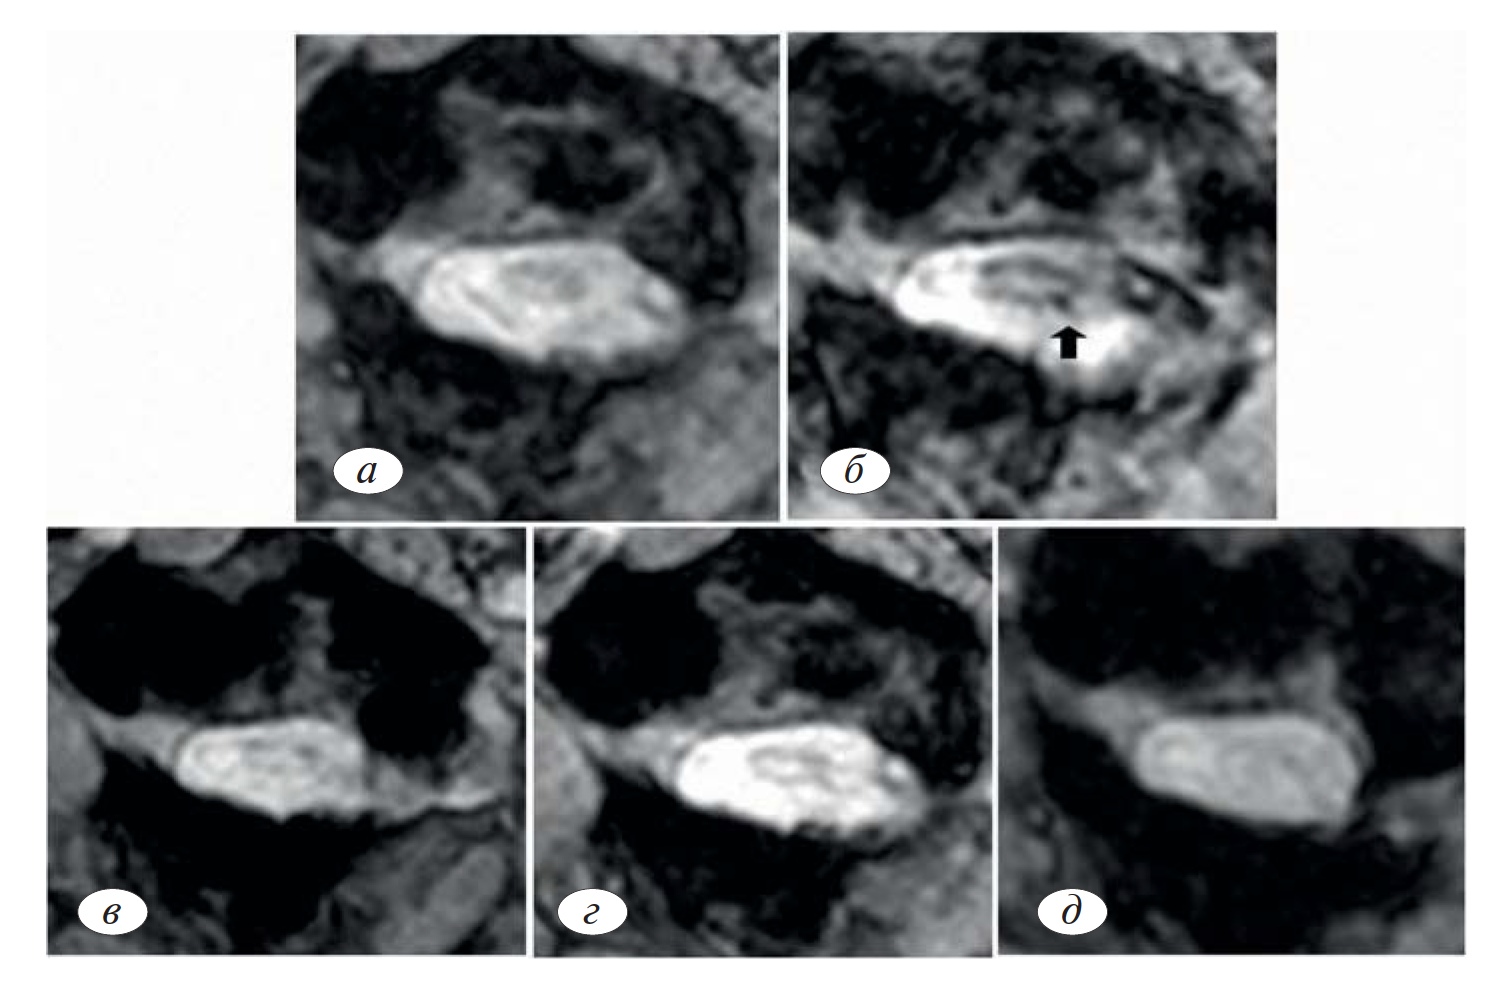

Рис. 18. МРТ-изображения сегмента СI спинного мозга, полученные в различные сроки после операции:а — состояние до операции; б — 2 сут после операции; в — 2 нед; г — 1 мес, д — 7 мес. Стрелкой показан очаг накопления меченных магнитными частицами стволовых клеток, который на более поздних МР-томограммах не определяется (по A. Chotivichit и соавт. [33]).

Fig. 18. MRI images of the segment CI of the spinal cord obtained at different times after surgery: a — state before surgery; b —2 days after surgery; b —2 weeks; g —1 month, d —7 months. The arrow shows the «hearth» of the accumulation of magnetic particles labeled stem cells, which later on Mr-tomograms is not defined (for Chotivichit A. et al. [33])